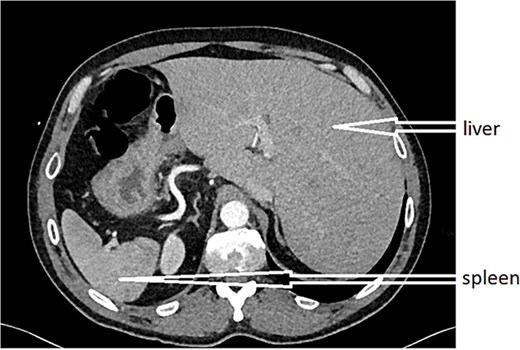

An urgent CT scan revealed situs inversus (Fig. 1) with left-sided high-positioned appendicitis (Fig. 2).